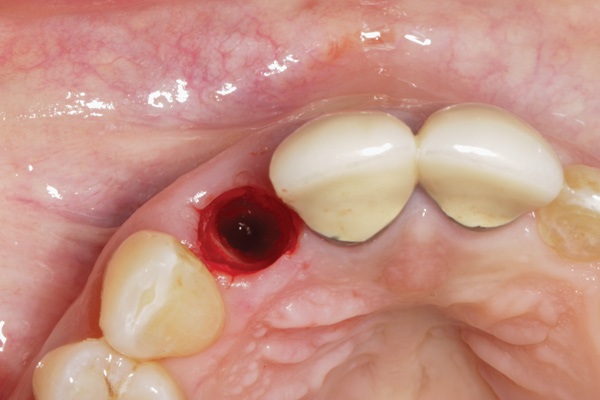

Fig 1. Clinical photograph showing significant issues related to implant midfacial mucosal recession and loss of interdental papillae. This is attributed to incorrect implant positioning (too buccal and too deep); several corrective surgeries resulted in interproximal bone loss, then loss of interdental papillae.

Figure 1

Buccally Positioned Implant

A minimum of 2 mm of facial bone thickness has been proposed as the “critical bone thickness” for the prevention of vertical height loss of the facial plate. It has been reported that when the distance of the buccal shoulder position of the implant to facial bone plate is below this critical thickness, an increased amount of facial bone resorption may be observed, which, in turn, may increase the chance of implant mucosal recession and failure (Figure 1). When the facial bone thickness is more than 2 mm from the implant buccal shoulder position, the likelihood of facial bone loss is decreased and the chance for alveolar bone stability is, therefore, increased.16